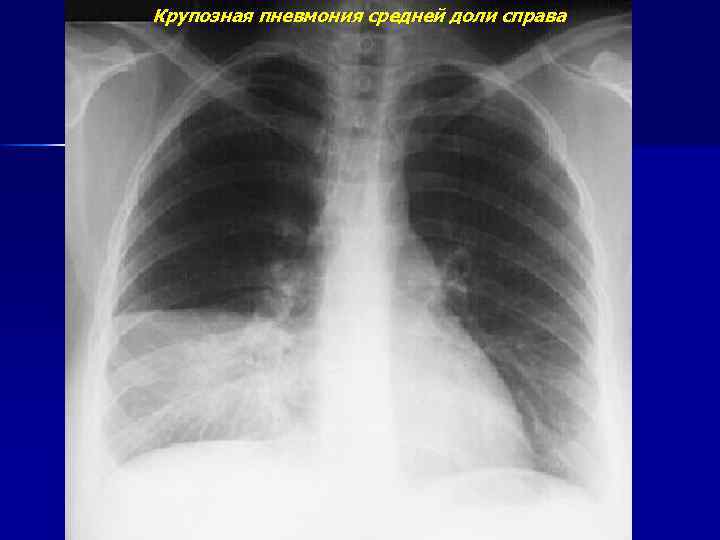

Крупозная пневмония средней доли справа

Крупозная пневмония средней доли справа (продолжение)